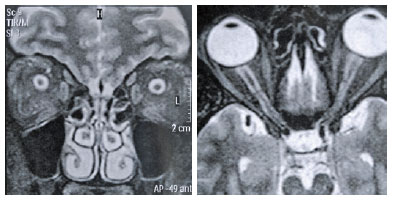

A 37-year-old woman complained of headaches following bilateral visual loss in the past two years, which had become more frequent in the past six months. She was obese and had undergone bariatric surgery three months earlier, followed by a considerable weight loss. In her first neuro-ophthalmic examination, she had visual acuity of 20/20 in both eyes; her pupils were equal in size and no afferent pupillary defects were present. Version was full and no other abnormalities were found on examination except the fundus finding of a bilateral swollen optic disk. Computerized analysis of the visual fields showed loss of the peripheral visual field in both eyes (Figure 1). Magnetic resonance imaging (MRI) of the brain and the orbits revealed flattening of the globe, an enlarged optic nerve sheath, protrusion and enhancement of the optic nerve head, and vertical buckling of the optic nerve (Figure 2). Lumbar puncture, including raquimanometry, was not available; however, our patient had objective signs of IIH, such as holocranial headache, obesity, tinnitus, and papilledema. The diag nosis of IIH was made with the presumption of good prognosis of visual function after the bariatric surgery. At six months after the bariatric surgery, the patient had no further headaches, 20/20 vision bilaterally, and better visual field findings on computerized analysis (Figure 1). However, the fundus examination revealed persistent mild papilledema in both eyes (Figure 3). Ocular B-scan ultrasonography showed optic disk drusen bilaterally (Figure 4).